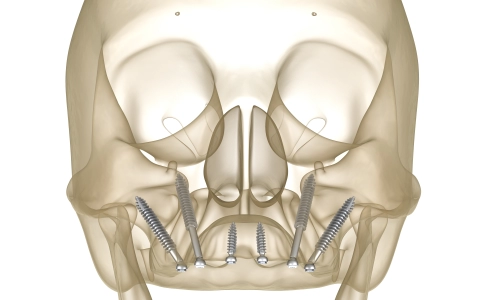

Zigomatik İmplant Tedavisi

Zigomatik implant, üst çenede kemik yetersizliğinde elmacık kemiğine yerleştirilen, aynı gün sabit diş sağlayabilen ileri implant çözümüdür.